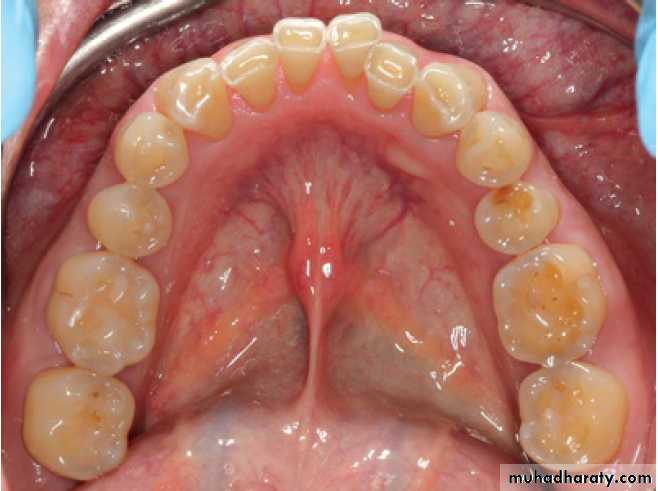

Examination of the Oral Cavity:

* the extent of accumulated food debris, biofilm, calculus, and tooth surface stains.

* Oral malodor, which is also termed fetor ex ore, fetor oris, or halitosis

* The lips, the floor of the mouth, the tongue, the palate, the vestibule, and the oropharyngeal region.